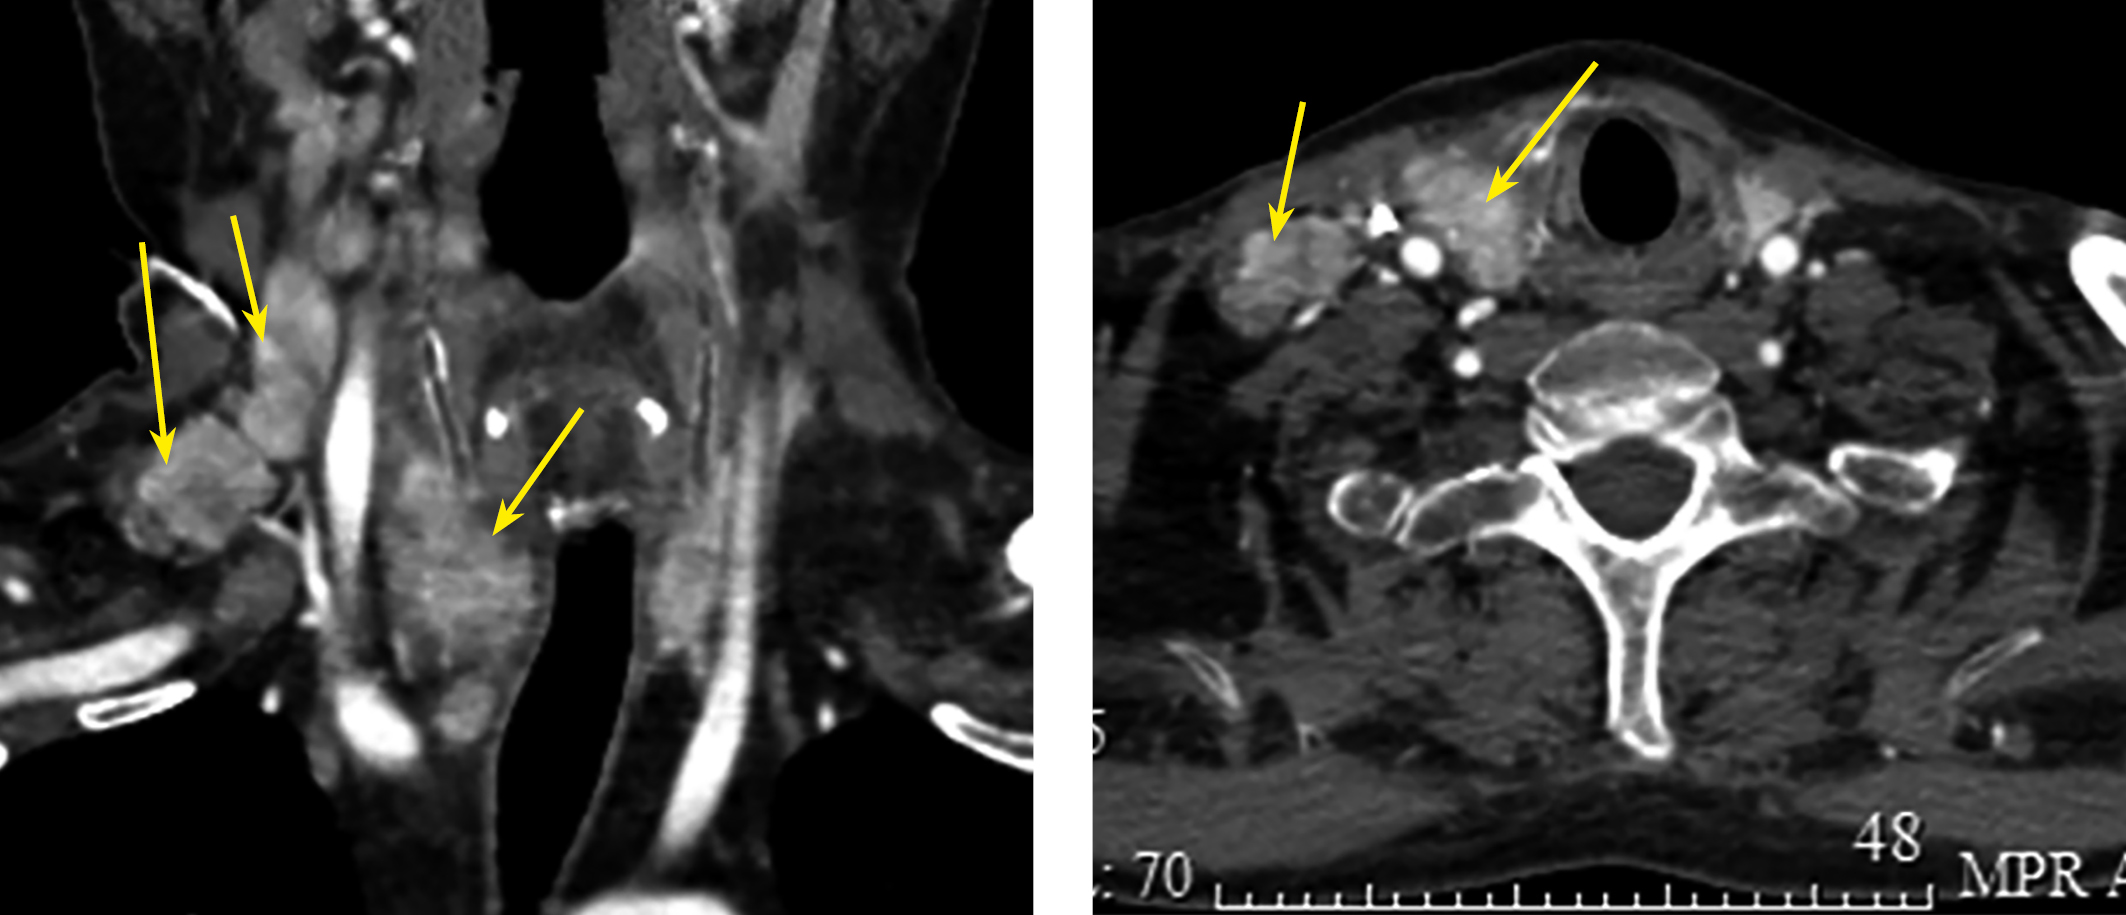

При компьютерной томографии (КТ) шеи с внутривенным контрастированием: правая доля ЩЖ увеличена в размерах за счет образования до 5 см, нижний полюс опускается до грудинного конца ключицы. Многочисленные увеличенные боковые шейные и паратрахеальные лимфоузлы размером до 2,5 см с патологическим накоплением контраста (рис. 2).

Рисунок 2. КТ шеи с в/в контрастом: образование правой доли ЩЖ — до 5 см, множественные центральные и боковые шейные лимфатические узлы с патологическим накоплением контраста.